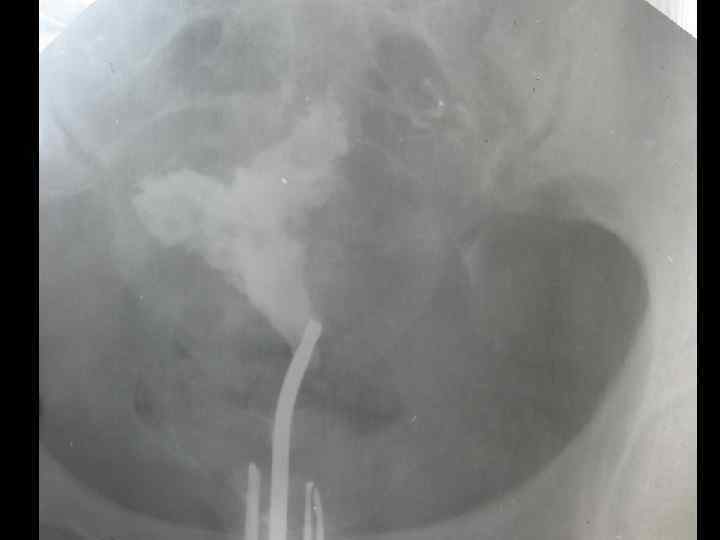

Диагностика эндометриоза • Анамнез. Тщательно собирают семейный анамнез у пациенток, наличие родственниц с эндометриозом. Обращают внимание на боли, нарушение менструаций, бесплодие в анамнезе. • Инструментальная диагностика. - Рентгенологические методы. При подозрении на аденомиоз гистерографию проводят на 5 -7 день менструального цикла с водорастворимым контрастом. Рентгенологическая картина характеризуется наличием законтурных теней.